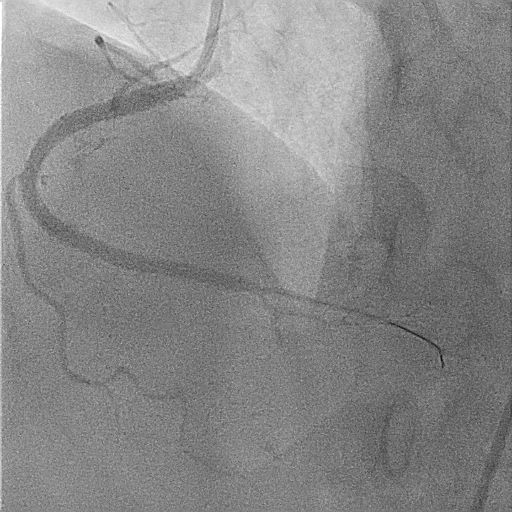

A 51-year-old man presented with stable angina and previously failed right coronary artery (RCA) CTO PCI. During RCA CTO PCI (Figure 1), the wire was inserted into the extraplaque space (Figure 2, Video 1). Intravascular ultrasound (IVUS) showed a hematoma (Figure 3A, Video 2). Live 3-dimensional tip detection IVUS wiring was successful (Figure 4, Video 3). A FineCross microcatheter (Terumo) was placed over the first wire into the extraplaque space and blood was withdrawn by connecting a negative indeflator to the microcatheter. Stents were deployed (Figure 5) and postdilated. Post-IVUS showed almost complete resolution of the hematoma (Figure 3B, C; Video 4) with good results (Figure 6, Video 5).